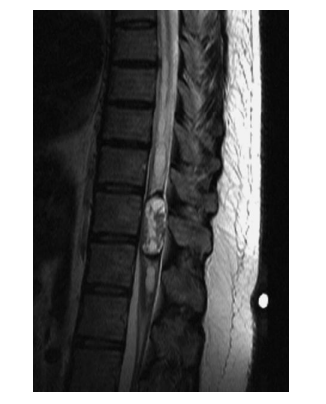

A 39-year-old presents with a 6-month history of tingling in her fingers and in the last few months, her legs. There is no bowel or bladder disturbance. On examination, there is cape-like pattern of pain and temperature loss in her upper limbs. Upper limbs are weak distally 4/5, and reflexes are globally brisk with extensor plantar responses bilaterally. MRI is shown. Which one of the following is most likely?

A 39-year-old presents with a 6-month history of tingling in her fingers and in the last few months, her legs. There is no bowel or bladder disturbance. On examination, there is cape-like pattern of pain and temperature loss in her upper limbs. Upper limbs are weak distally

4/5, and reflexes are globally briskwithextensor plantar responses bilaterally. MRI is shown. Which one of the following is most likely?

a. Astrocytoma

Astrocytomas are the second most common intramedullary spinal cord tumors in adults (30%),

compared to children in which they are the commonest. Almost 60% of these tumors occur in the cervical and cervicothoracic region, and 20%

have an associated syrinx. Back pain and motor

deficits are the most common presenting symptom in astrocytomas. The most significant prognostic factors in patients with primary spinal cord

astrocytoma are tumor histology, tumor grade,

age, and performance status. Because of the rare

nature of this disease, almost all data are based

on retrospective reviews fraught with selection

bias. Therefore, neither the extent of resection

nor treatment with adjuvant irradiation appears

to be prognostic, although this is controversial.

The classic MRI appearance of intramedullary

astrocytoma is cord enlargement with a central

lesion with poorly defined margins, cysts, peritumoral edema and patchy enhancement (no

enhancement in 30%). It is typically isointense

to hypointense on T1-weighted images and

hyperintense on T2-weighted images. The treatment of choice for intramedullary astrocytomas is complete excision of the tumor, when it can be safely accomplished without neurologic compromise. Otherwise, an incomplete excision is typically performed for grade I lesions, and biopsy alone is the surgical strategy for the

non-exophytic component of an infiltrative glioma. GTR is typically extremely difficult to

achieve because of the infiltrative nature of all

but the pilocytic lesions, with most authors

reporting a 0-50% likelihood of GTR for spinal

cord astrocytoma. In patients with favorable

prognostic factors (low-grade histologic findings,

good performance status, and young age), observation with serial imaging studies, reserving irradiation for local recurrence, is an appropriate

management option, particularly for young children. Radiation should be considered for highgrade tumors, inoperable tumors, tumors remaining after surgery, and recurring tumors. In the remainder of patients, adjuvant irradiation is

usually recommended because progression of

tumor in the spinal cord may lead to significant

neurologic impairment. The overall outcomes

are similar for patients with low-grade gliomas

of the spinal cord treated either by GTR or

STR or biopsy followed by external beam irradiation (EBRT), with most series reporting OS at

5 years of 55-100%. With high-grade tumors in

adults and children, the median survival time is

quite poor (4-10 months) despite surgery and

EBRT. Extrapolating from the results of Stupp et al. for intracranial glioblastoma, temozolomide

has emerged as a treatment strategy in high-grade

intramedullary tumors